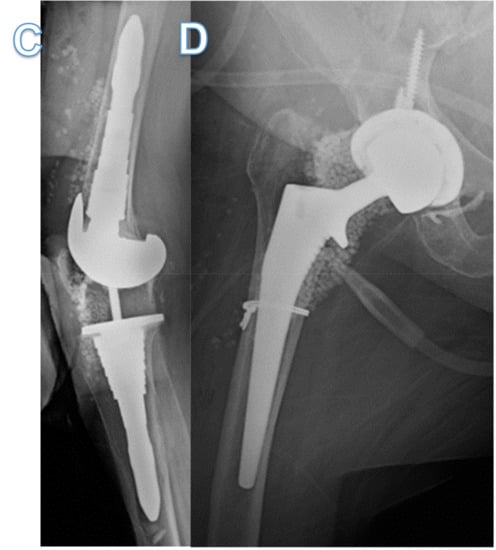

2. Case